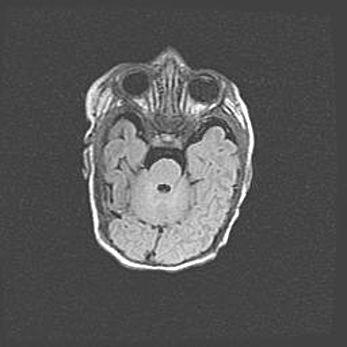

Множественные кисты обоих полушарий головного мозга, наибольшая из них в правой затылочной области. Ассиметричная атрофическая гидроцефалия.

Возраст: 7 месяцев

Вес: 5660 г

Пол: мужской

Окружность головы: 41,5 см

Срок гестации: 28-29 недель

Кисты головного мозга развиваются в результате многоочаговых некрозов вещества мозга и возникают вследствие перенесенной перинатальной инфекции, менингитов, энцефалитов, асфиксии, родовой травмы, расстройств мозгового кровообращения различного генеза. Образованию кист в веществе головного мозга плодов и новорожденных способствуют такие факторы, как высокое содержание в нем воды, недостаточная (или отсутствие) миелинизация и слабая астроглиальная реакция на повреждение.

Кисты могут сочетаться с гидроцефалией и другими поражениями головного мозга.